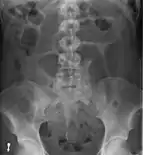

- Abdominal x-ray – tire-like shadow arising from right iliac fossa and passing to left

An x-ray of a person with a small bowel volvulus.

Plain X ray of a cecal volvulus